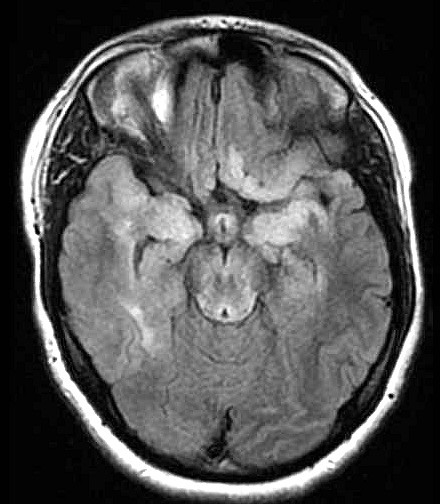

| Fem. 17a. |

| Nódulo sólido homogêneo preenchendo o III ventrículo, com limites precisos, com hipossinal em T1 e hipersinal em T2 e FLAIR, que se impregna por contraste paramagnético. Lesão menor implantada no assoalho do IV ventrículo provavelmente representa disseminação por via liquórica. |

| CORTES AXIAIS, T1 COM CONTRASTE | ||

| F. 17a. Tumor teratóide rabdóide atípico de III ventrículo. RM | HE | VIM, GFAP | HHF35, desmina, 1A4 | AE1AE3, EMA |